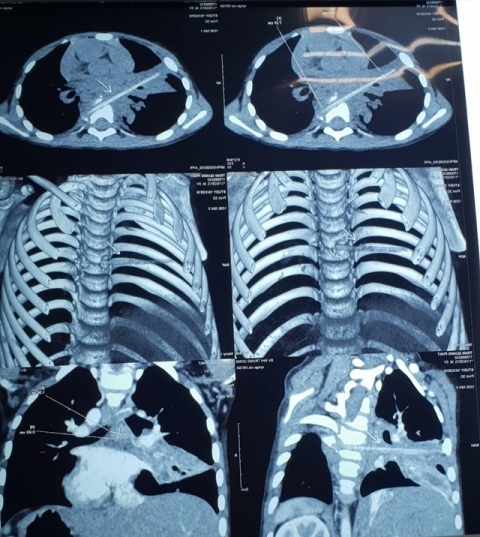

TS. BS Nguyễn Lý Thịnh Trường, Giám đốc Trung tâm Tim mạch trẻ em, Bệnh viện Nhi TƯ cho biết, sau khi siêu âm, bác sĩ phát hiện van động mạch chủ tim của bệnh nhi bị tổn thương rất nặng do vi khuẩn tạo thành khối sùi đã ăn mòn hết. Bệnh nhi có hiện tượng dọa phù phổi, có thể đột tử bất cứ lúc nào.

Để phẫu thuật, bác sĩ đứng trước hàng loạt thách thức như bệnh nhi còn quá nhỏ, van tim không có sẵn, phương pháp sử dụng chính màng tim tự thân để tạo lá van cũng không khả thi, trong khi chưa thể xác định chính xác các cơ quan xung quanh có bị vi khuẩn tấn công hay không. TS Trường cho biết, đây là trường hợp mắc bệnh lý van tim phức tạp nhất từ trước đến nay.

Nói rõ hơn về trường hợp cháu V., TS Trường cho biết, bệnh nhi vốn có bệnh lý tim bẩm sinh, sau đó bị vi khuẩn xâm nhập qua đường máu rồi khu trú ở van động mạch chủ, sau đó ăn mòn dần bộ phận này.

Bình thường, máu trong động mạch chủ chảy 1 chiều, ngăn không cho trào ngược về tim. Khi van động mạch chủ tim bị hỏng, máu bị trào ngược, gây áp lực lớn lên buồng tim, gây suy tim, phù phổi.